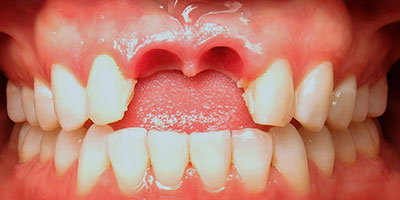

Se toma radiografía periapical con el radiovisiografo, encontrando zona radiolúcida periférica a los dos alvéolos, al retirar la férula los dientes se salen solos en condiciones desfavorables para su reinserción periodontal.

Radiografía Periapical

Dientes Centrales